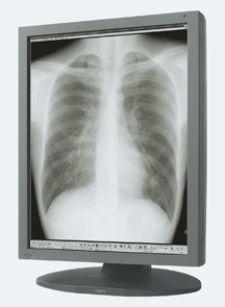

U.S. Electronics Inc. will introduce two new medical-grade high-luminance monochrome LCD displays, offering a full array of features. The new high-contrast USEI/Totoku ME355i2 3 MP and ME253i2 2 MP monitors support a broad range of diagnostic imaging modalities, including CT, MRI and high-speed 3-D image rendering. Utilizing Totoku’s Luminescence Uniformity Equalizer technology, both models provide consistent light intensity across the entire display face, eliminating uneven brightness at the periphery. An 11.9-bit lookup table (LUT) delivers ultra-high grayscale DICOM conformance for a distortion-free image.